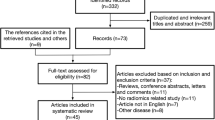

According to the PRISMA statement, a comprehensive research of the literature was performed to find relevant articles on the applications of texture analysis and radiomics to 18F-FDG PET/CT in lymphomas. Information on the general, methodological and clinical aspects of all included studies was collected. Studies were divided into three groups depending on their clinical aim: (1) outcome prediction; (2) histological differentiation from other malignancies; (3) assessment of bone marrow involvement.

Twenty-seven full-text papers were selected for final review, 17 of which aimed to predict outcome, prognosis or survival, 7 tried to differentiate lymphoma from other malignancies and 3 studies aimed to assess bone marrow involvement.